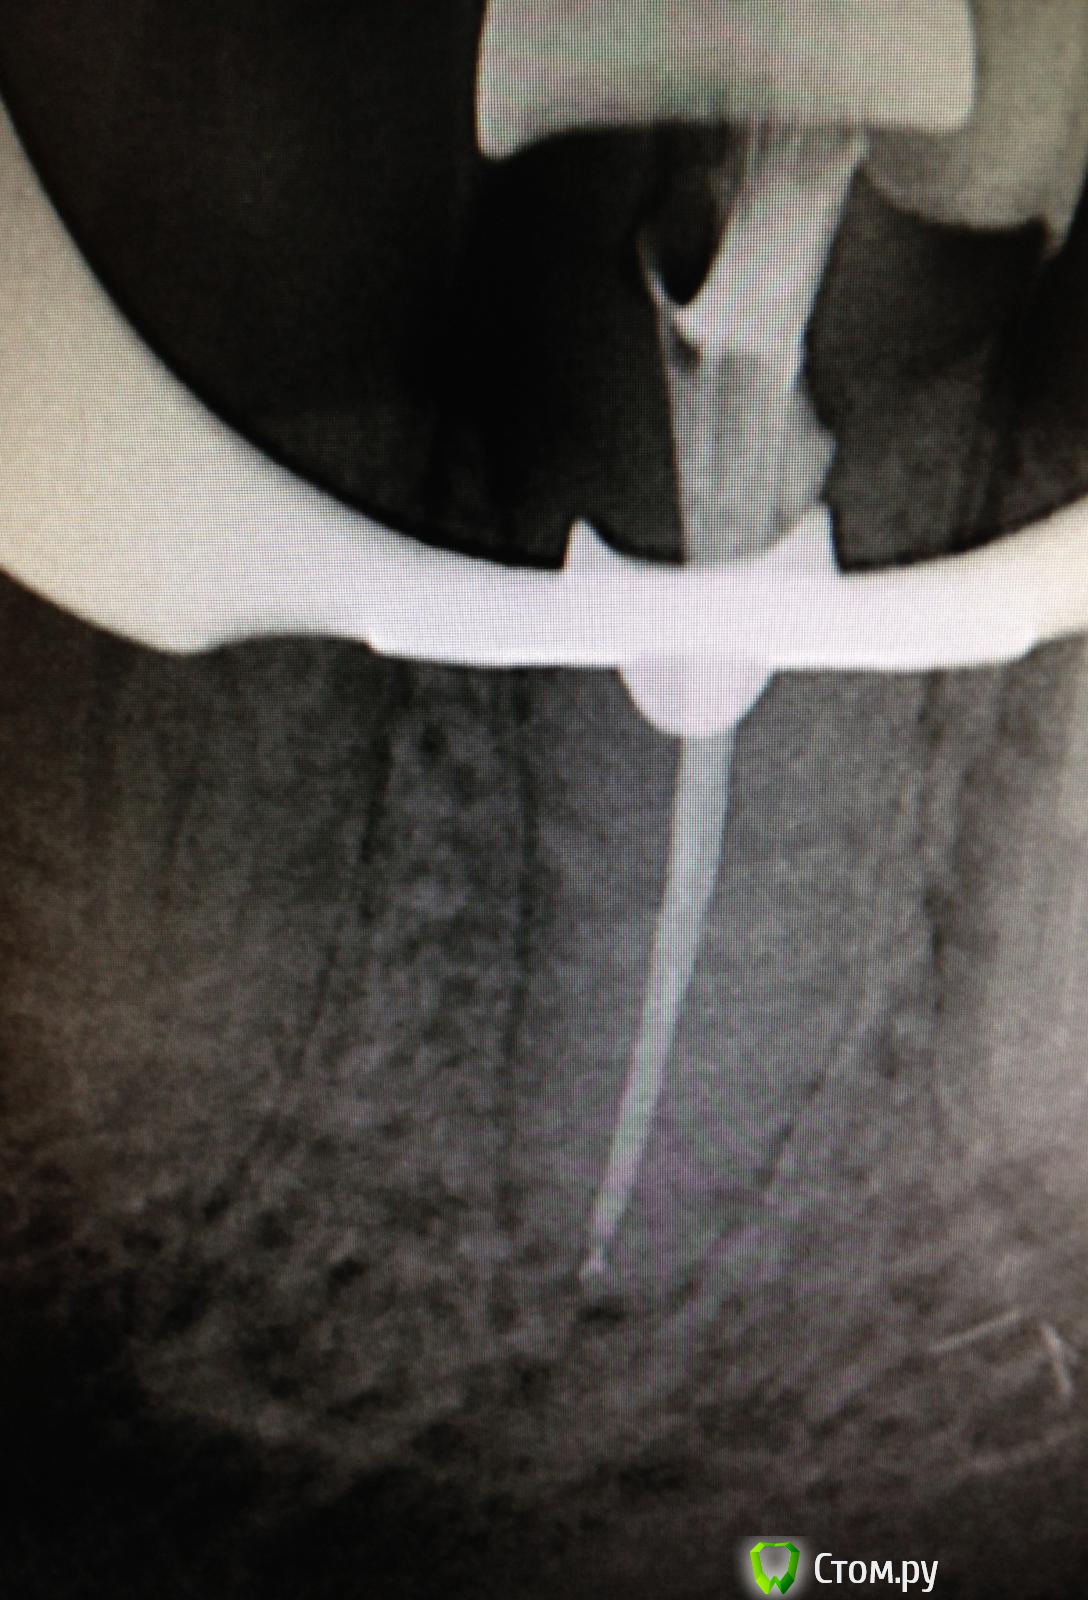

SSTi Опубликовано 22 августа, 2014 Автор Поделиться Опубликовано 22 августа, 2014 16. Резорцин. Убрал пломбу цементную, в небном наполовину пусто. Другие надо искать. В первый визит - коффер, уз аккуратно поездили по дну. Откопали мб. 15ка на 1 мм заходила. Полностью обработал небный и прошел на 2/3 мб. Кальций. Второй визит - коффер, нашел дб и мб2(сходится с мб через 3-4 мм). Расширились. Помылись. Ломанули профайл 20.04 в дб, обошли, помыли еще, озвучили и достали. латералка. Не идеально. Но для рф и это прекрасно. 1 Ссылка на комментарий

Shaid Опубликовано 22 августа, 2014 Поделиться Опубликовано 22 августа, 2014 Нормально) я бы отломок только часа два доставал) Где сломался? Ссылка на комментарий

SSTi Опубликовано 22 августа, 2014 Автор Поделиться Опубликовано 22 августа, 2014 (изменено) Нормально) я бы отломок только часа два доставал) Где сломался?В дистальном в средней трети. Да его легко было обойти. Потом подцепил чуть и вымыл. Даже не успел огорчиться Изменено 22 августа, 2014 пользователем SSTi Ссылка на комментарий